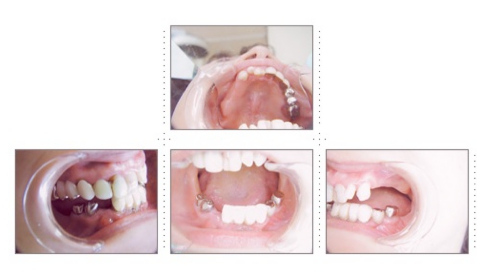

症例10

64才 男性

地元の有名寿司屋さんの店主の方(インプラント患者さん)からの御紹介です。

上顎の義歯をインプラントに変えたいとの希望で来院されました。

このケースはまずはじめに局部床義歯を作り直します。インプラント部と義歯床が接触するのを避ける為、部分的に床を削れるようにクラスプ、補強線の位置を決定します。顎骨の質・量ともに十分で、インプラント埋入は簡単です。右側4本のインプラント埋入は8分で終わりました。3ヶ月後には残存歯全て抜歯し、フルブリッジタイプの仮歯をセット。仮歯の段階で十分に咬合のチェックをし、3~4ヶ月抜歯窩の治癒を待ち最終的にフルブリッジへと移行します。